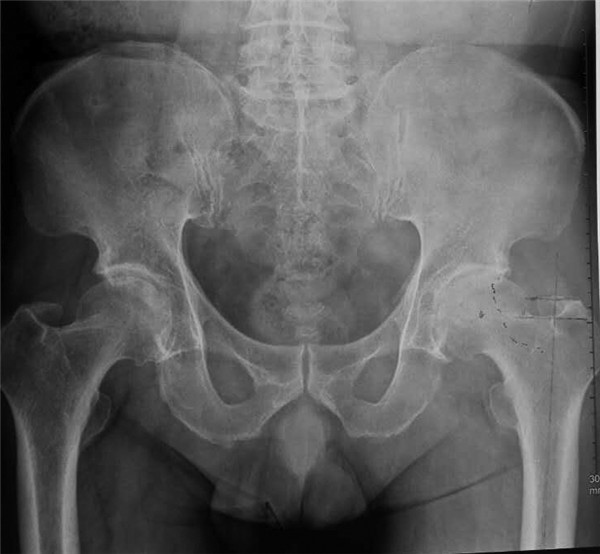

近日,由我院骨科王坤正教授带领王春生副教授、杨佩副教授、张子琦博士等人组成的优秀手术团队,在我院麻醉科手术科的全力配合下,完成了西北地区SuperPATH微创人工全髋关节置换术。手术过程非常顺利,患者术后康复状况良好。

微创全髋关节置换微创化是关节外科医生一直探索的目标。SuperPATH的出现,让我们真正看到了微创全髋关节置换时代的到来。并非切口越小就越微创,微创技术并不单单指切口的大小,切口小仅仅是微创手术的一个特点,而不是微创手术追求的唯一目标,如果片面地为了追求小的手术切口,过多损伤关节周围的肌肉、韧带,手术部位暴露不充分,致使手术假体安装的位置不准确,反而是因小失大,得不偿失,在保证手术部位得到充分显露的基础上,更重要的是保护关节运动所依赖的韧带和肌肉,尽量使切口越短越好。SuperPATH技术手术切口长度6cm--8cm;不需要切断外旋肌,经梨状肌和臀小肌的间隙进入,几乎保存髋关节周围所有的肌肉功能;几乎保留了完整的关节囊;手术操作过程中不需要外科脱位(术中不造成肢体极度的旋转与扭曲); 髋臼侧仅仅要求1cm的皮肤切口就可以完成。